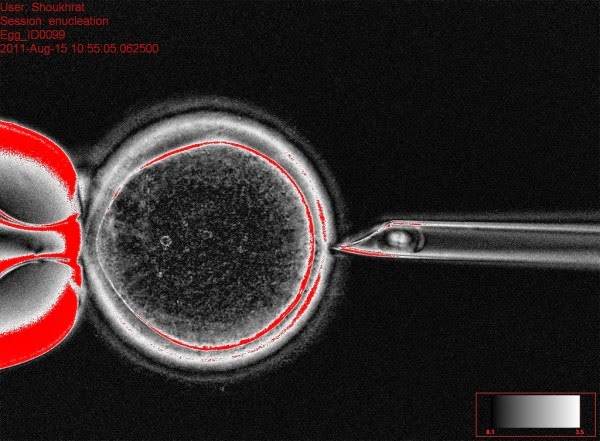

The technique for removing the nucleus from an egg [Courtesy Oregon Health Sciences University ]

Three parent embryos called safe. A scientific review panel in the United Kingdom has issued a report saying that a controversial fertility treatment that uses three parents is likely to be safe. The in vitro fertilization technique is being developed to help women who carry rare genetic mutations have healthy children. While we inherit most of our DNA from the chromosomes in the nucleus of mom’s egg and dad’s sperm, a small organelle outside the nucleus, called the mitochondria, also carries a few genes. Those we inherit only from mom, since her egg hosts those at the point of fertilization. This technique puts mom’s nucleus into the egg of a healthy donor that has had its nucleus removed but still has the healthy mitochondria. Gretchen Vogel, who worked with me as an intern several years ago, did a nice job explaining the process in Science Insider.